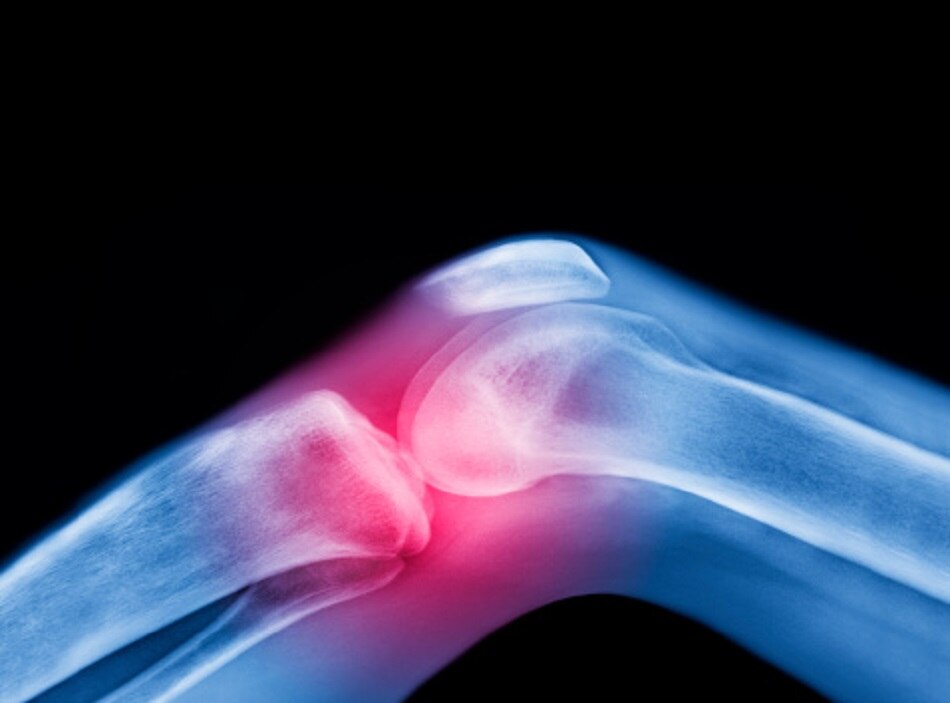

लेकिन आर्थराइटिस (गठिया) को किसी अन्य लक्षण के बिना, सिर्फ एक लक्षण के आधार पर नहीं पहचाना जा सकता है. क्रेपिटस के अलावा कुछ अन्य लक्षण जैसे कि जोड़ों में दर्द ऑस्टियोआर्थराइटिस के संकेत हो सकते हैं. जोड़ों में अकड़न भी खासतौर से सुबह के वक्त या इनैक्टिविटी पीरियड के बाद ऑस्टियोआर्थराइटिस का वॉर्निंग साइन हो सकती है.

इससे प्रभावित जोड़ों की गति में भी धीमापन आ सकता है. ब्रिटेन में आर्थराइटिस के प्रति लोगों को जागरुक करने वाली संस्था 'वर्सज आर्थराइटिस' का कहना है कि कई तरह की परिस्थितियों में एक इंसान ऑस्टियोआर्थराइटिस का शिकार हो सकता है. 40 साल से ज्यादा उम्र के लोगों में इसका जोखिम ज्यादा होता है. इसके अलावा औरतों और ओवरवेट लोगों में भी इसका खतरा ज्यादा रहता है.

इसके अलावा यदि किसी व्यक्ति को पहले कभी ज्वॉइंट इंजरी हुई हो या कोई व्यक्ति जन्म से ही असामान्य जोड़ों के साथ पैदा हुआ हो, उनमें भी इसका खतरा ज्यादा रहता है. वर्सज आर्थराइटिस के मुताबिक, विरासत में मिलने वाले जीन्स भी हाथ, घुटने और कूल्हे पर ऑस्टियोआर्थराइटिस का कारण बन सकते हैं. ऑस्टियोआर्थराइटिस के कुछ रूप सिंगल जीन के म्यूटेशन्स से भी जुड़े होते हैं, जो कॉलेजन नाम के एक प्रोटीन को प्रभावित करते हैं.

ऑस्टियोआर्थराइटिस के लक्षण प्रगतिशील नहीं होते हैं. मतलब ये समय के साथ खुद-ब-खुद बदतर नहीं हो जाते हैं. दरअसल, ऑस्टियोआर्थराइटिस में आपका सबसे दर्दनाक समय पहली बार लक्षण दिखने के कई साल बाद भी हो सकता है. लक्षण सामने आने के कुछ साल बाद कुछ लोगों की स्थिति पहले की तरह समान रह सकती है या उसमें सुधार भी आ सकता है. वहीं कुछ लोग जोड़ों में दर्द के कई चरणों से गुजर सकते हैं.